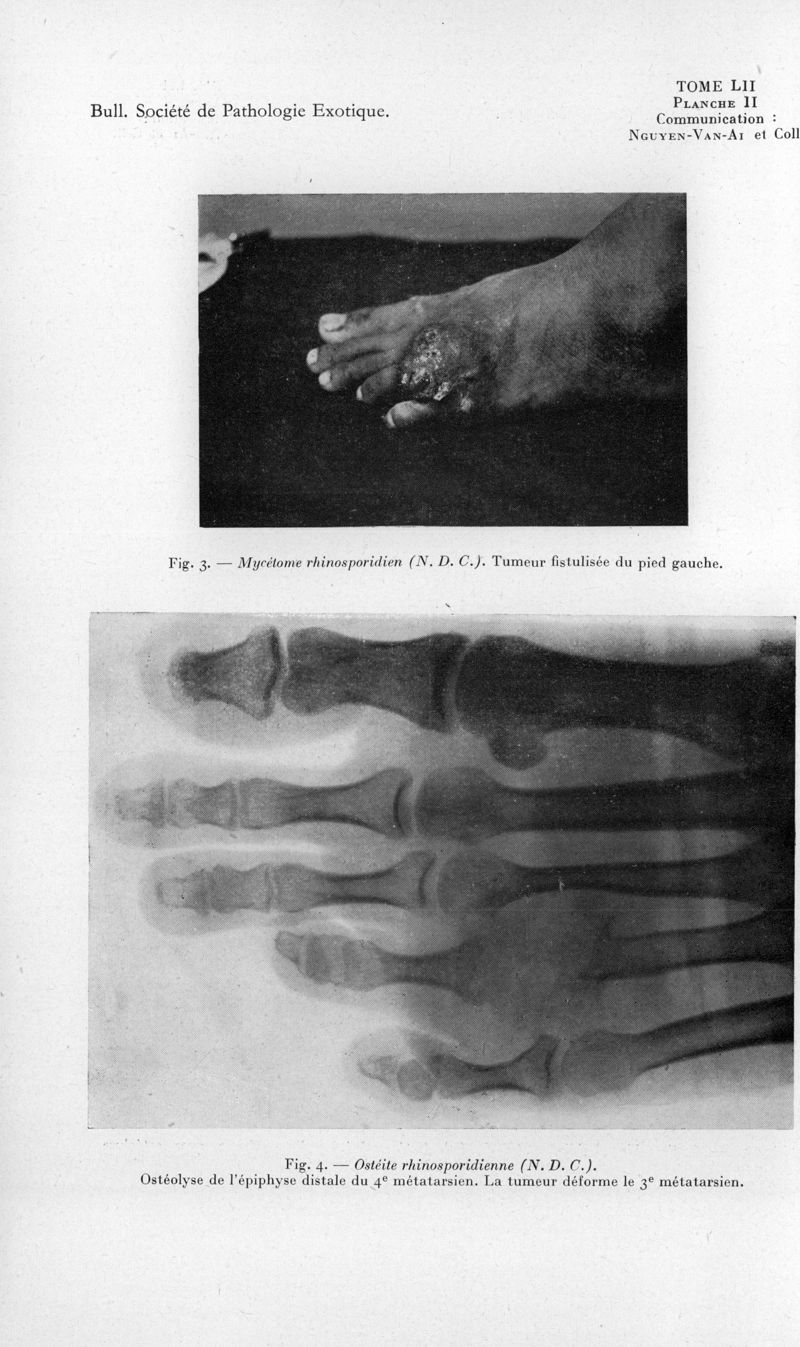

Bulletin de la Société de pathologie exotique et de ses filiales

1959, tome 52. - Paris : Masson, 1959.